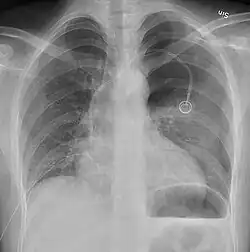

Image from a computed tomography (CT) scan of the chest. On the right (left side of the patient) there is a black area suggesting free air inside the chest

CT scan of the chest showing a pneumothorax on the person's left side (right side on the image). A chest tube is in place (small black mark on the right side of the image), the air-filled pleural cavity (black) and ribs (white) can be seen. The heart can be seen in the center.